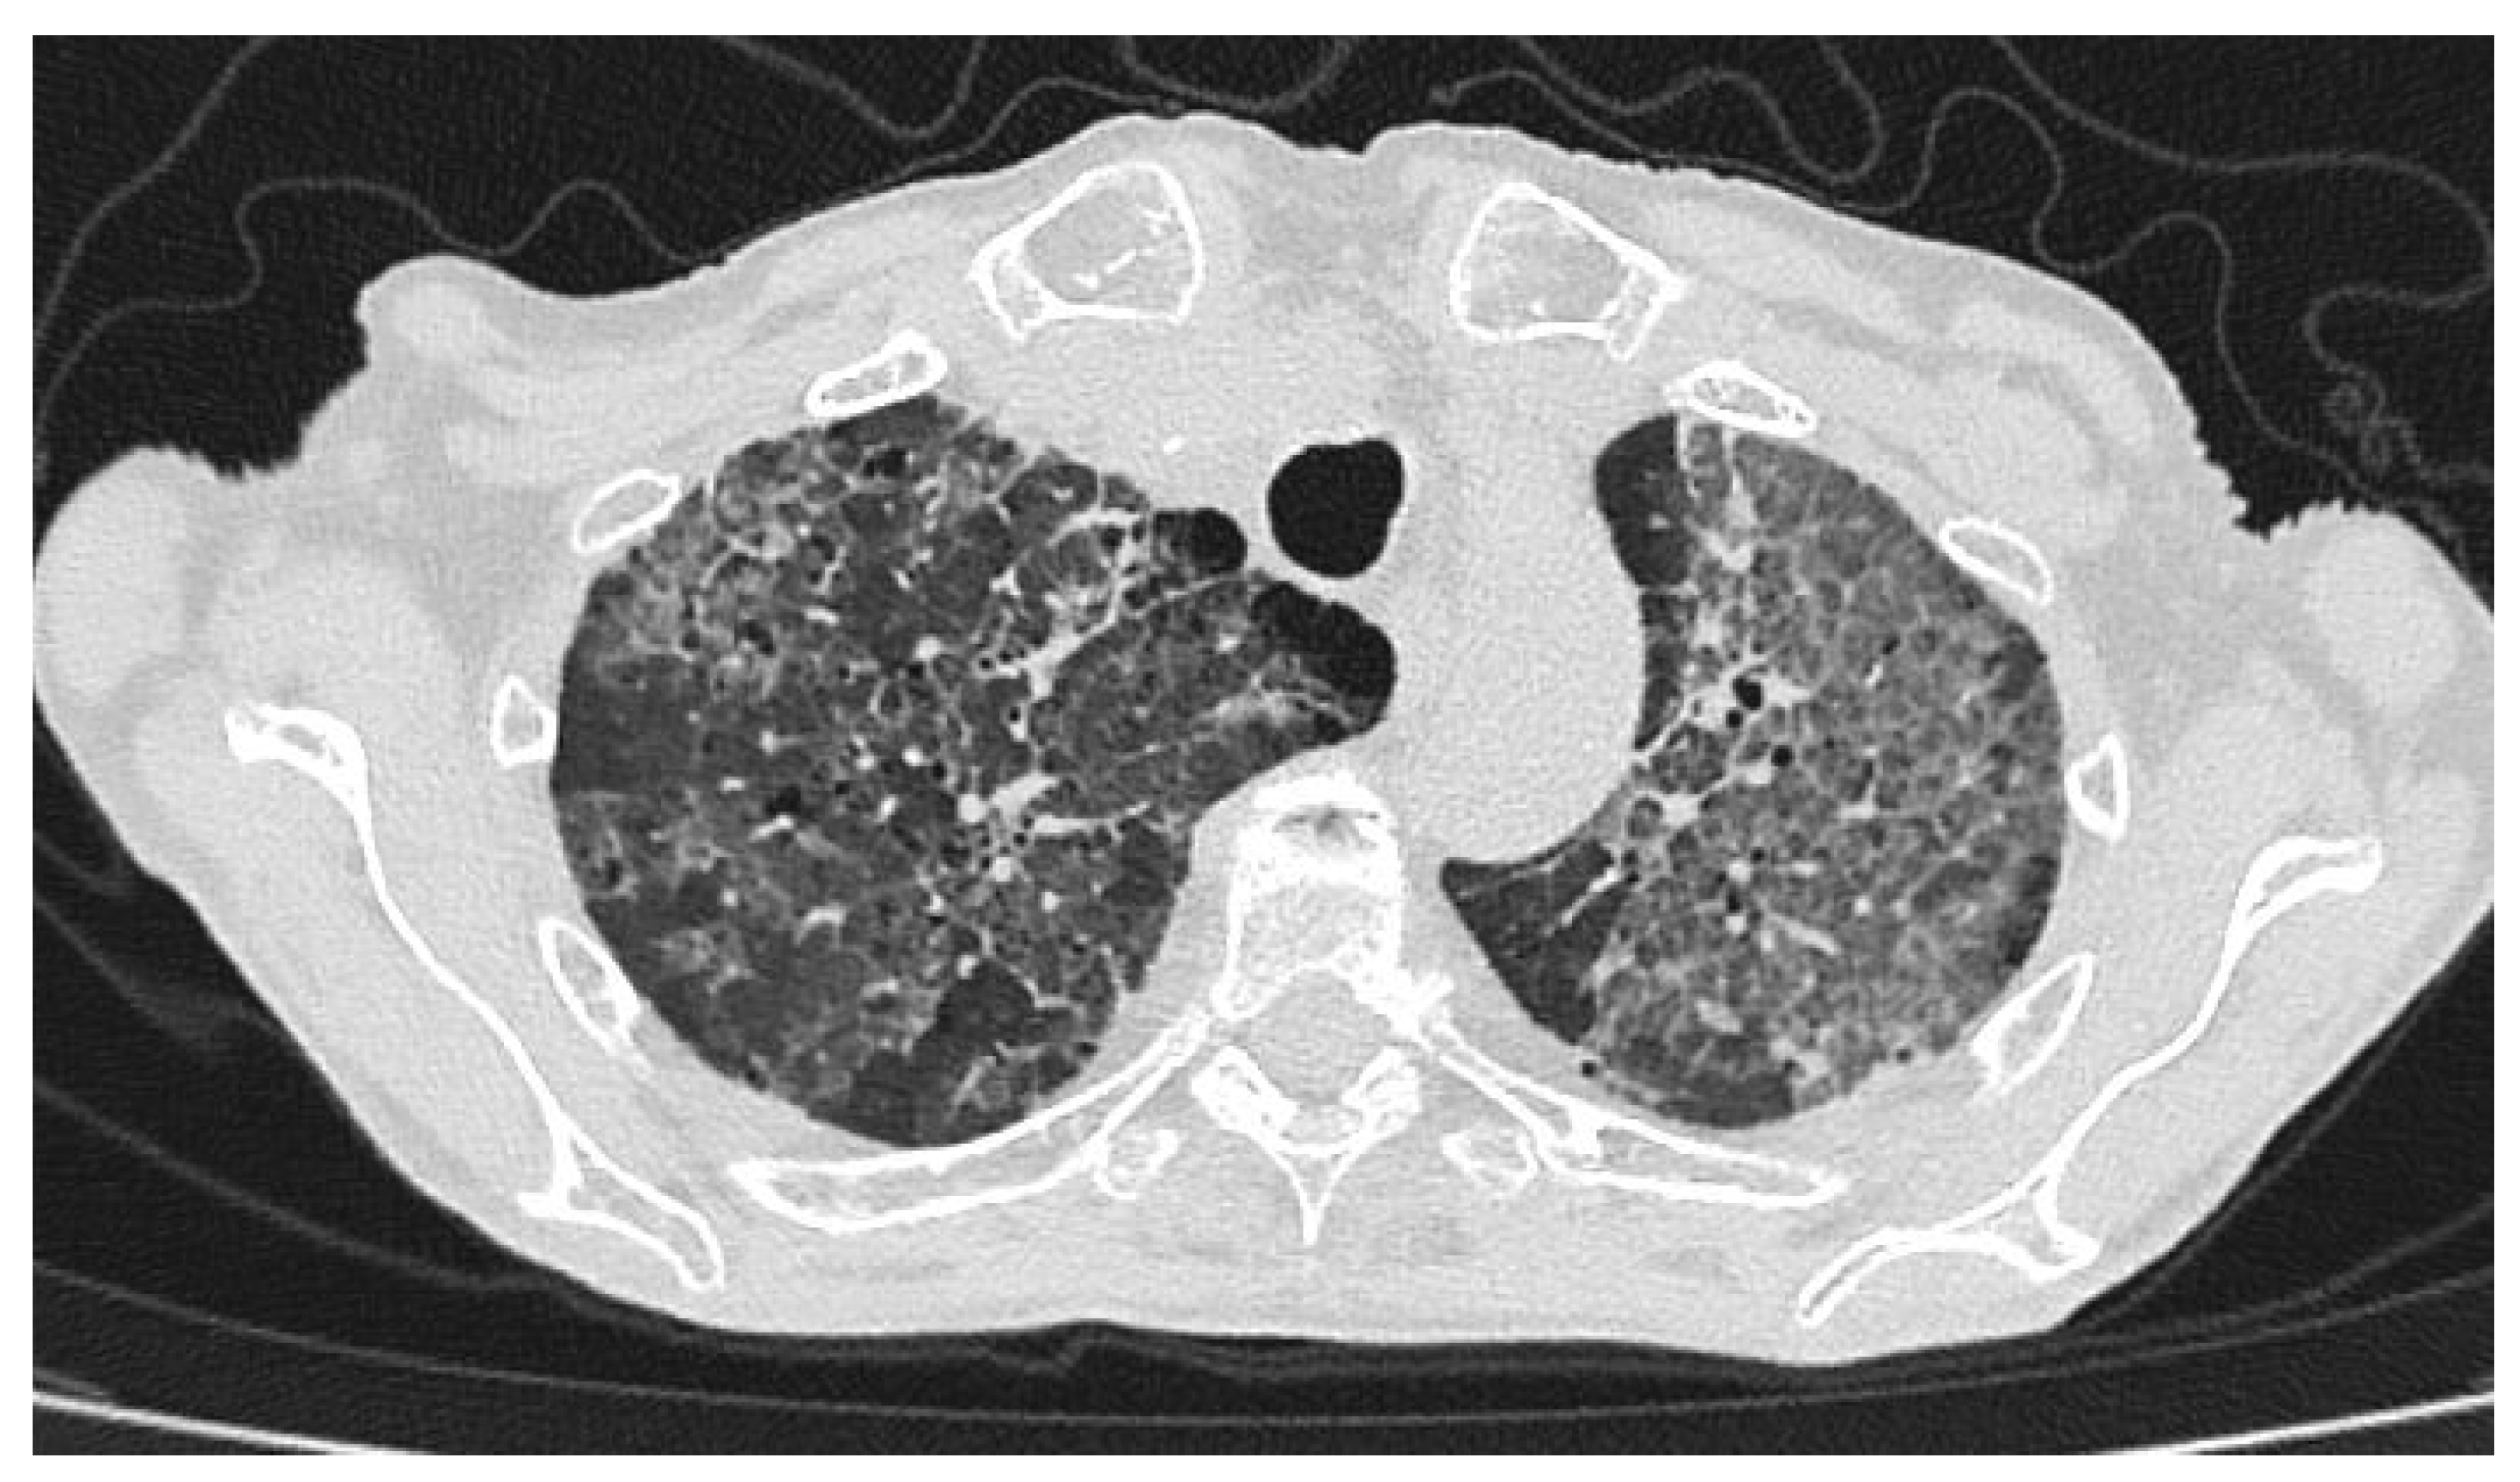

Mixed Infectious–Immune Pneumonitis Associated with PD-L1 Blockade: A Case of Durvalumab-Induced Lung Injury Complicated by Human Metapneumovirus Infection

2. Case Presentation